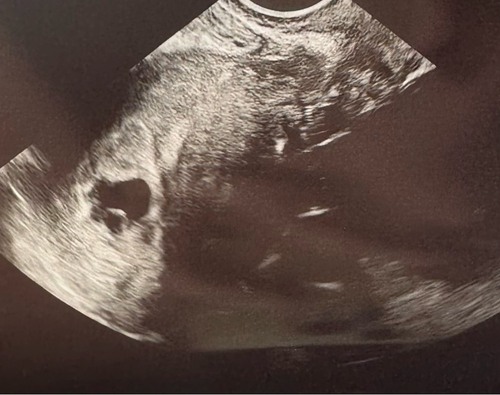

Vandaag de eerste echo gehad (rond de 6 weken). Er waren twee vruchtzakjes zichtbaar waarvan eentje met een kloppend hartje. 馃挄 nu hopen dat het goed blijft gaan. Over 1,5 week weer een echo 馃馃徑

Hier ook een kloppend hartje! Ik ben teruggezet naar 6+1. Wel een hartvormige baarmoeder. De verloskundige was er niet zo ongerust over, wel meer kans op vroeggeboorte of een keizersnede. Ik laat het even bezinken en voor nu is het een mooi plaatje zo 馃グ